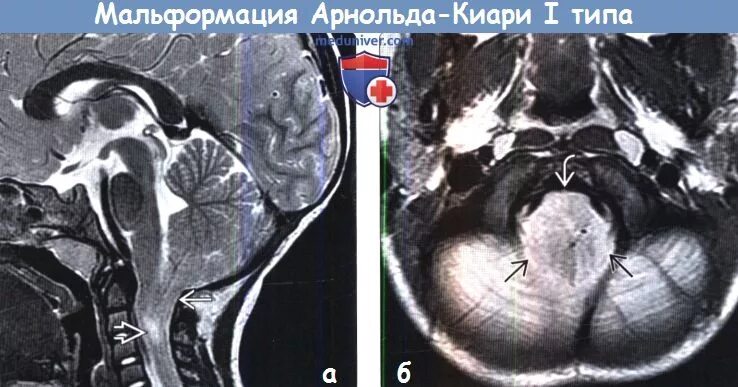

Мальформация арнольда киари типы